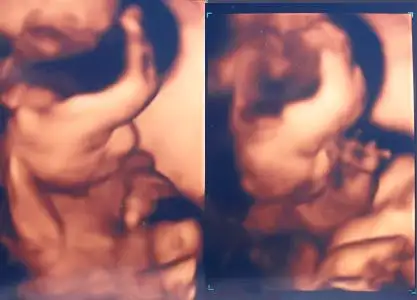

:64::64::64::seni bekliyorduk süperrrrrrrrr resim harika

tombul yanaklar belli tontiş olduğu

çok güzel gözünaydın fmg maşallahhhhhhh:nazar::nazar:

ne kadar netttttttttt

ne kadar saclııııııııııı

ne kadar tatlıııııııııı

ayyy Allah nazardan korusun :nazar::nazar::nazar::nazar::nazar::nazar::nazar: